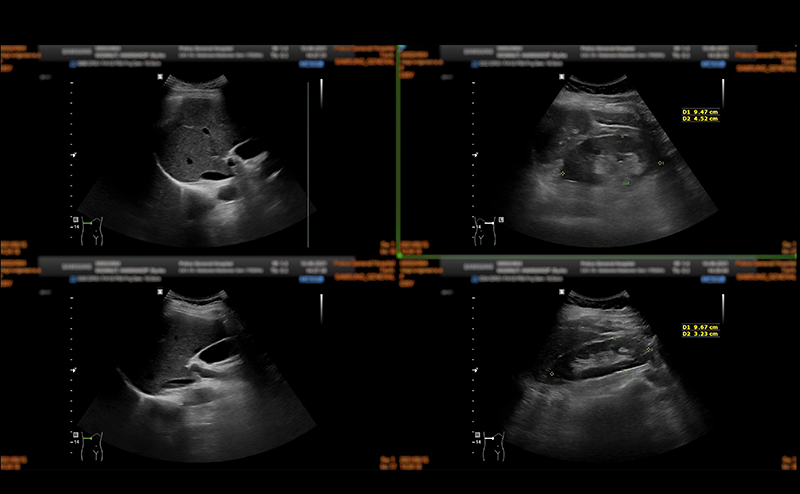

Compounding this phenomenon is another physical property of waves, known as phasicity. When two waves of the same frequency line up, such that their peaks and troughs are the exact same, they are said to be “in-phase.” Two in-phase waves undergo constructive interference where the amplitude of each wave is summed together to create a new wave with increased amplitude. When this wave with increased amplitude is received by the ultrasound machine, it is given a brighter shade of grey and is seen as brighter on the screen.  In contrast, two waves that have their peaks and troughs in exact opposite positions, are known as “out-of-phase.” This results in deconstructive interference where both waves cancel each other out. In this case, no sound signal is received by the machine and appears as anechoic on the screen.

The overall effect of diffuse reflectors causing constructive and deconstructive interference across the entire tissue, gives the ultrasound image a speckled or grainy appearance. See Figure 1. In reality, the tissue is not grainy or speckled at all. Rather the ultrasound machine interprets the tissue as having a grainy texture because of how sound interacts with diffuse reflectors and due to in-phase and out-of-phase waves. This speckling is known as “speckle artifact.” Overall, this is not desirable in an ultrasound image. In particular, this speckle artifact leads to poor demarcation of tissue interfaces and fails to show subtle differences that should be present in adjacent tissues. To reduce speckling, ultrasound manufacturers use a variety of post processing algorithms. These algorithms are proprietary and differ from one manufacturer to the next. Often, a particular post-processing function or feature responsible for reducing speckle is given a name by the manufacturer. Table 1 lists the four vendors we met with and the name of the feature that reduces speckle.

Lipliner_Fig1.pngFigure 1. Constructive and Deconstructive Interference of Diffuse Reflectors on Ultrasound Images